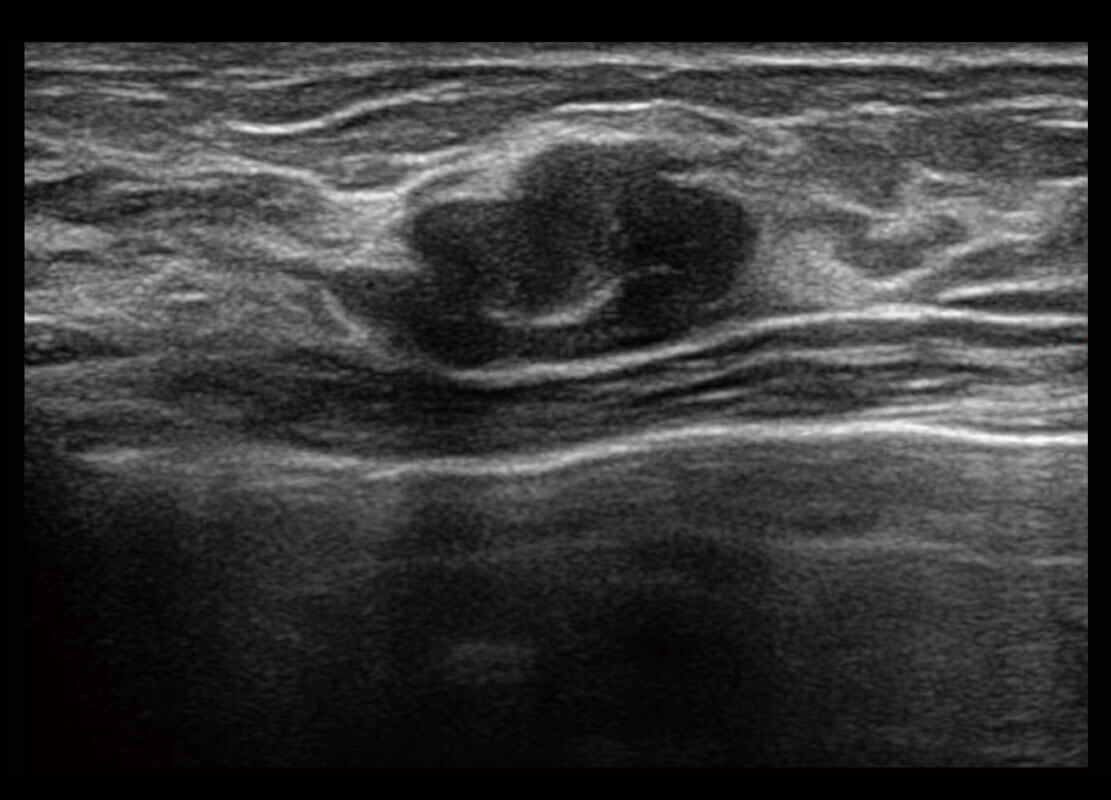

乳腺超声 / 新生儿

P60搭载宽频带线阵探头、宽景成像、弹性成像技术,为您提供乳腺应用方案。P60支持高频相控阵探头、线阵探头、腹部高频探头、腹部微凸探头等,丰富的探头群搭载敏感的彩色血流成像,适用于新生儿多种脏器检测要求,满足新生儿筛查需求。

• 乳腺导管癌